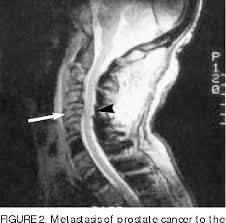

Metastatic Spine Tumors

Metastatic Spine Tumors from embed.widencdn.net